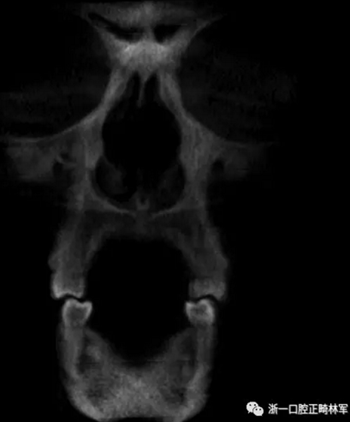

然而,CBCT成像也具有較大的限制:有限的分辨率,牙體組織的不準確表現,以及當患者在咬合位或者完全牙尖交錯位CBCT掃描時,上頜骨和下頜骨牙齒之間發生的混合(圖1)。 這種混合使上頜骨與下頜骨牙齒的自動分離復雜化,并且由于咬合解剖結構和細節的不準確而使人工分離變得困難。

圖1. 在CBCT中咬合時上頜牙齒和下頜牙齒咬合面的混合和咬合細節的喪失。